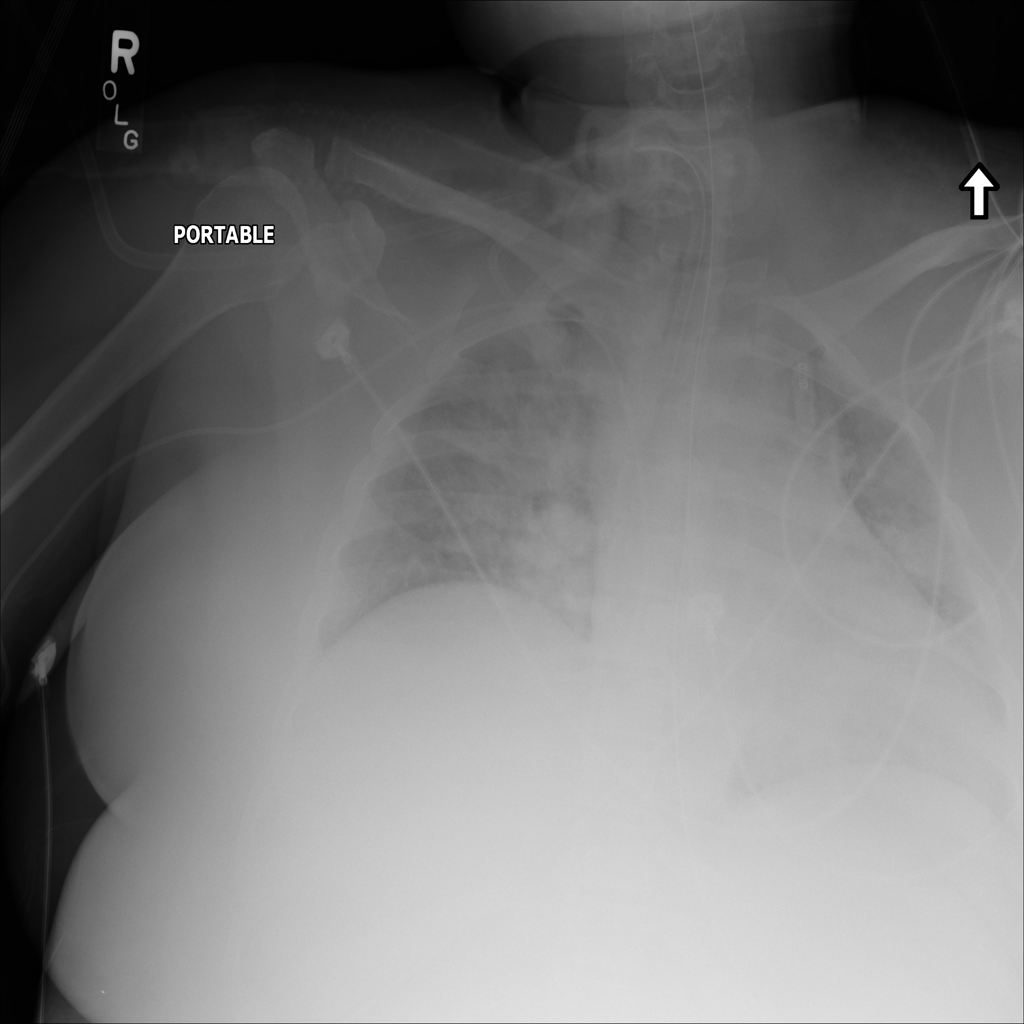

PAT-E828 · IMG-004Edema

PAT-E828 · IMG-004

AP